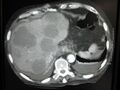

CT image of multiple liver metastases